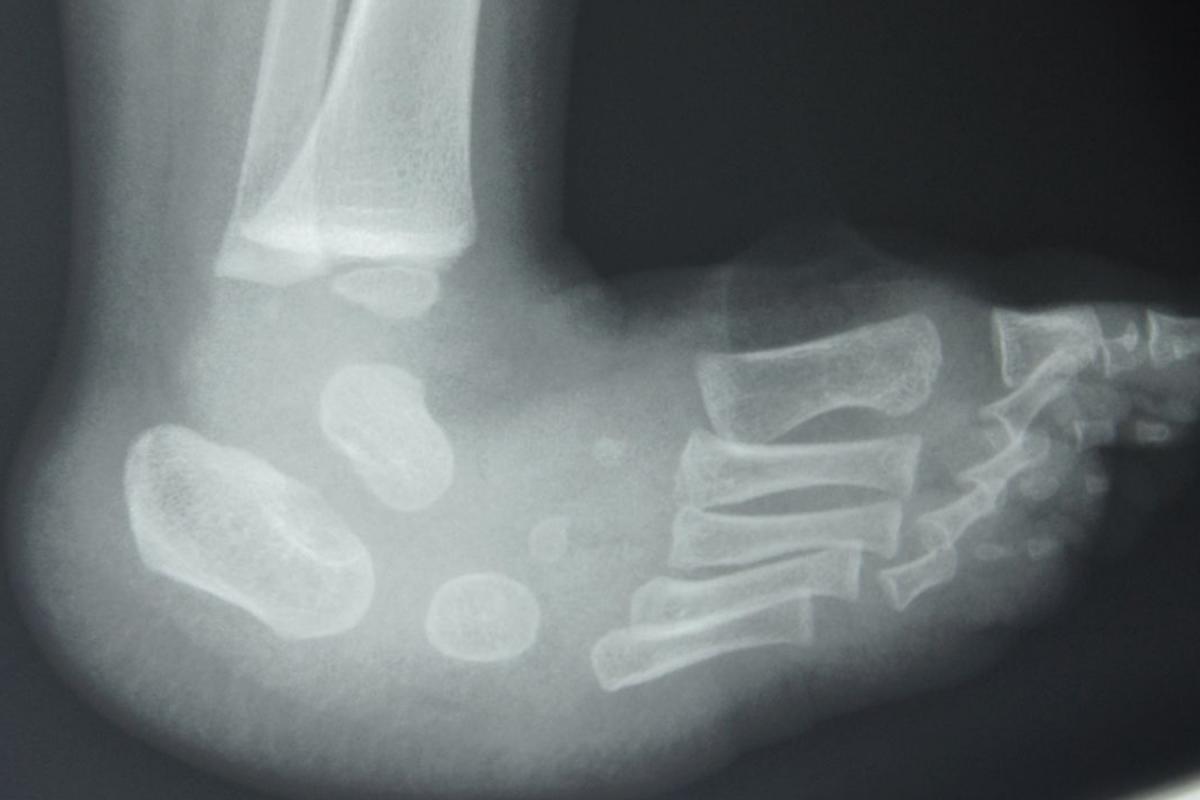

Briefly, treatment begins with identifying the morbid anatomy. Radiographs are unreliable and unlikely to enter into initial decision-making so they are rarely necessary to begin treatment. The surgeon initially palpates the ankle area at the malleoli and then brings his or her fingers and thumb distally to identify the talar head, noting that the navicular is displaced on the plantar and medial aspect of it.